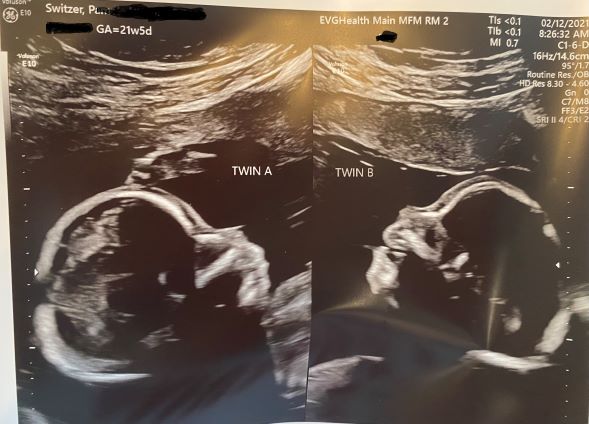

02/12/2021 – 21w5d | No surgery, cardiology appt – another day in the win column

Today’s Summary | No surgery equals a win

After staying overnight in a hotel .25 miles from the hospital to make sure I could get there no matter how much snowfall we received overnight, my 2.5 hours + of ultrasound and Doppler studies showed that everything remained approximately the same, so in short – no surgery today! Hoorayyy! We’re making peace with the reality that no action is good, no worsening news is great news, and the longer we can put off any procedures of any kind of poking or surgically going into the womb is a win. “No action” is not intuitive nor does it feel right: never before in our lives when facing a problem has doing nothing made sense. Yet, every day that we do nothing, we cross off the calendar as a win on on our march toward healthy viability (April 1) because it is a success. Onward we march.

More details from today’s Surgical Team/MFM visit

Amniotic fluid is measured via Maximum Vertical Pockets (MVP) which have a small +/- because the uterus isn’t a fixed shape like a sphere. Each time they measure, the uterus shape is slightly different and the measurement is taken by finding the deepest area in a vertical line, without the baby or any of his parts in the line. So the measurement varies a bit day-to-day by nature of the shape.  Today, it was approx. 6-7 cm for our smaller baby, Joshua and approx. 13.5-14.5 cm for our larger baby, Daniel. Total fluid remains at about 20 cm which is right on the line for causing contractions and cervical failure which leads to premature labor.

Doppler flows measured approx. the same, too.

Cervical length (which is discussed because it is the determining factor in all of the above) measured a bit better after two days of almost complete side-lying horizontal rest at approx. 3 cm up from 2.5 which is nearing the shortness that requires cerclage due to it basically failing to hold under the weight of all that fluid plus the babies.